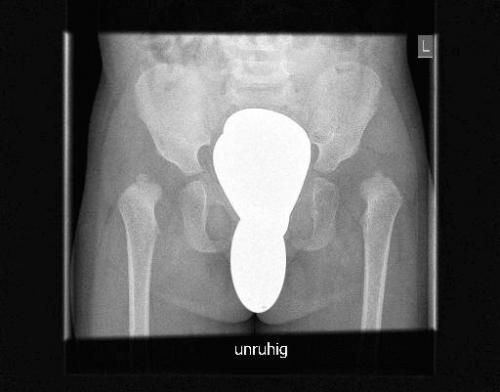

Ацетабулярные углы норма таблица. Углы тазобедренных суставов у детей: виды, зависимость нормы от возраста, определение на УЗИ и рентгенограммеИзмерение углов тазобедренного сустава у детей проводится при подозрении на врожденную дисплазию. Вовремя оказанная медицинская помощь многих спасает от инвалидности во взрослой жизни, ведь дисплазия — это нарушение в формировании сочленения. Страдают им преимущественно девочки в результате неправильного внутриутробного развития, частого пеленания, недостатка витаминов и минералов. Точной причины до сих не установлено.

Ацетабулярные углы норма таблица в 1 год. Размеры углов и возраст ребенка

В зависимости от возраста ребенка, показатель ацетабулярного угла и другие измерения могут быть разными. Норма ацетабулярных углов в 3, 4 и 6 месяцев отличается по своему значению. В три месяца нормальный угол находится в диапазоне от 25 до 30 градусов, к полугодию — от 20 до 25, после двух лет размер угла колеблется в пределах 18-23 градусов.

Это важно ! В некоторых случаях существующие индивидуальные особенности приводят к сдвиганию углов на 1-2 градуса. А норма это или патология может решать только врач. Для удобства можно привести таблицу, которая показывает норму углов:

Возраст ребенкаАцетабулярный угол

До 3 месяцев25 (+5)

4-6 месяцев21 (+5)

7-9 месяцев20 (+5)

10-12 месяцев18 (+4)

1 г.-1,5 года19 (+4)

1 г. 7 мес.-2 года18 (+4)

2 г.-2,5 года17 (+3)

2 г. 7 мес.-3 года16 (+3)

3-4 года15 (+3)

4-5 лет13 (+4)

5-7 лет11 (+3)

7-9 лет10 (+3)

9-10 лет9 (+3)

10-13 лет8 (+3)

13-14 лет9 (+3)